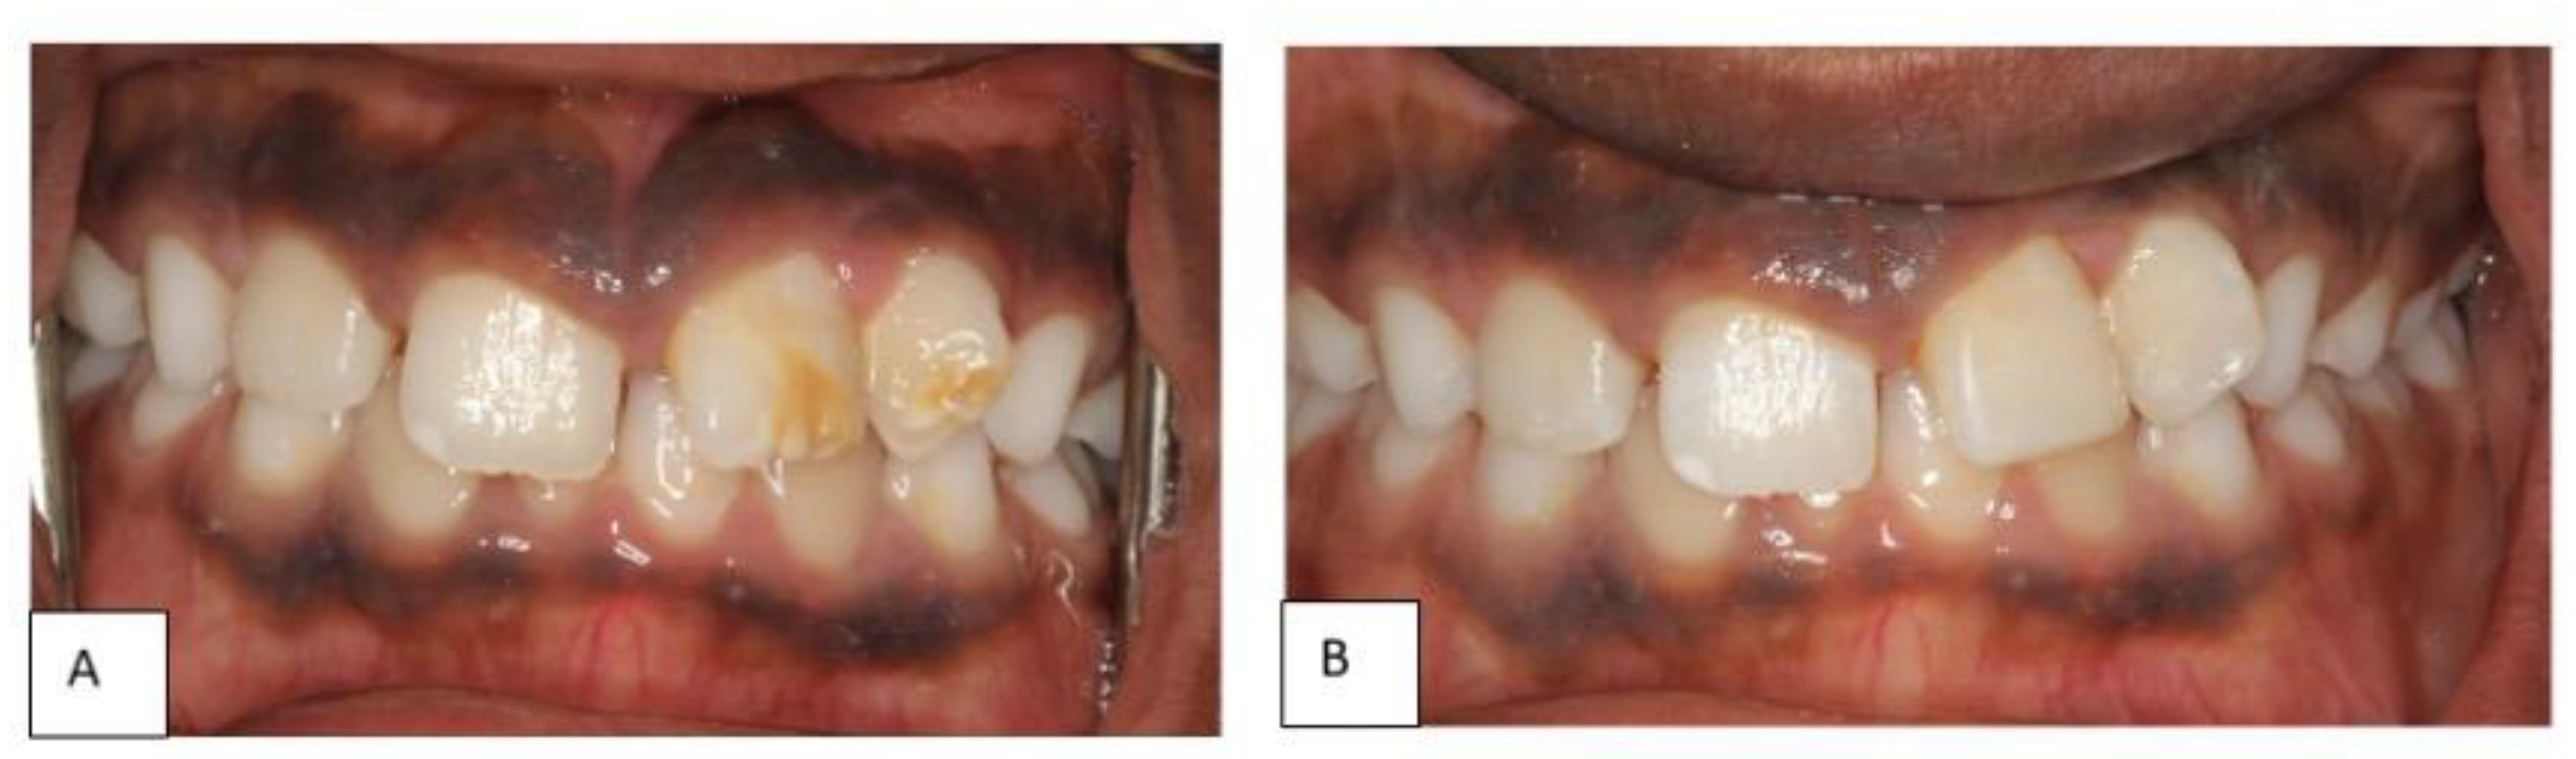

Following complete eruption of the affected permanent incisors, aesthetic restorations were provided with light-cured composite (Z350; 3M ESPE, St. Paul, MN, USA), using a minimally invasive cavity preparation (Figure 5). The aesthetic improvement re-established the patient’s self- esteem, and controlled tooth sensitivity. The patient was then referred for orthodontic treatment for correction of the malalignment.

Figure 5.

(A) the patient’s teeth at a 2-year follow up showing almost complete eruption of upper incisors. (B): the hypoplastic teeth after restoration with direct resin composite.